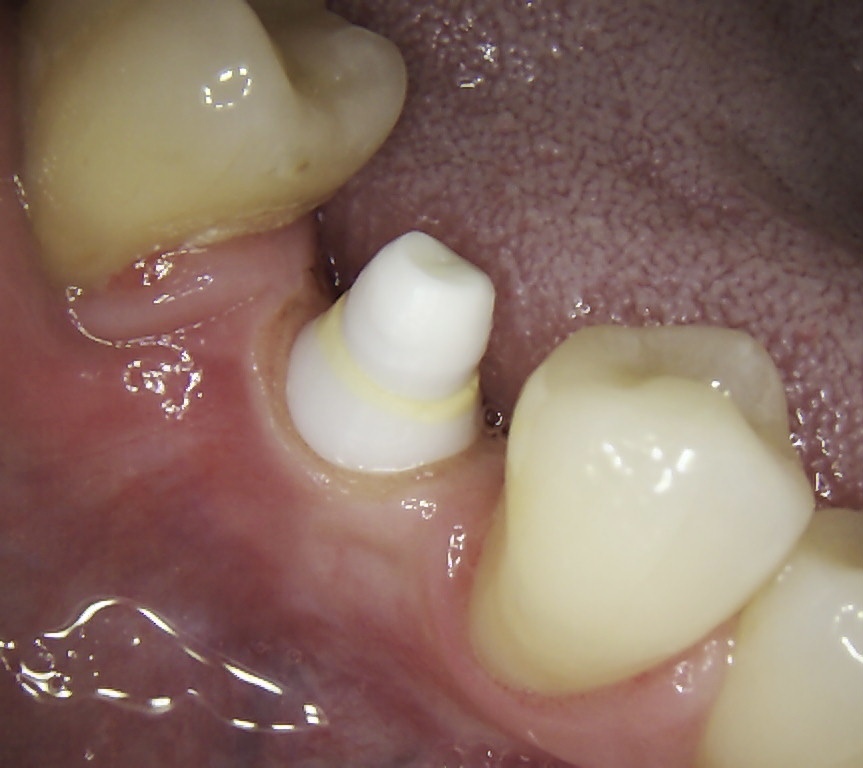

After 6 months of successful

orthodontic treatment, we were finally able to place the implant and the

provisional crown. After 4 months of ingrowth, aligners were removed and a full

ceramic crown was placed. The treatment was successfully completed!✋🏽😉